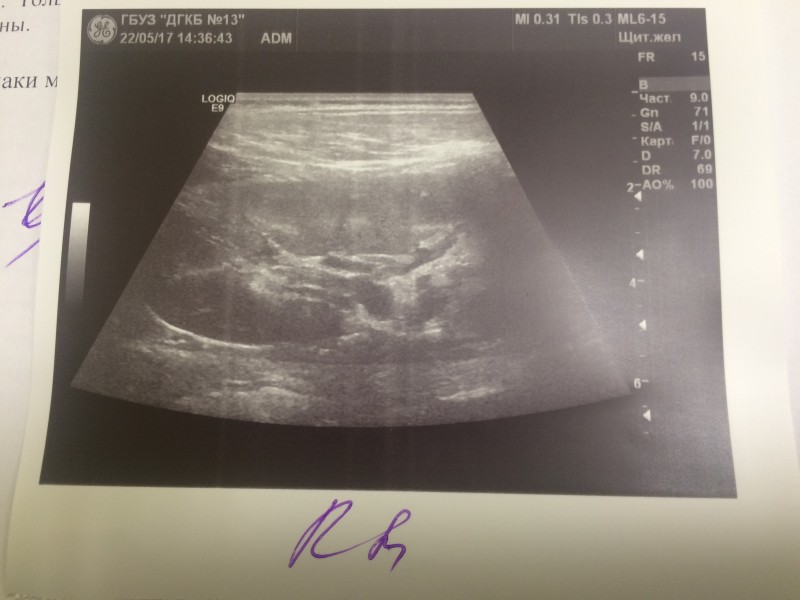

Пробегали от участковых врачей, до специалистов в Филатовской. Пока бегали, сдвали постоянно анализы и делали УЗИ. Итоги не ясны.

ещё. А файлы .pdf не могу выложить - пишет, недопустимый формат. Там анализы крови и мочи: 22/04/17 - белок в моче - 0,164 24/04/17 - белок в моче - 0,265 27/04/17 - клинический анализ крови: Нейтрофилы(общ.число), % 38.3, Лимфоциты, % 50.8, креатинин 51, мочевина 3,6

У дочки всё в порядке. Возвращаюсь к истории сына. Все анализы в норме, но одна киста выросла до 4 см в диаметре. Специалисты Филатовской больницы решили её склерозировать, учитывая удобное прилежание. Назначили госпитализацию на 4 февраля. 5-го КТ перед операцией, потом сама операция. Надеются убирать "проколом". Интересовался ваптанами. Ценник во всех странах отличается на 1-2 Евро... Неподёмный пока для нас, учитывая, что и "побочка" у препаратов есть, не кислая.

Операцию временно отложили на пару дней. По результатам КТ решили две кисты склерозировать после пунктирования, а одну иссекать лапороскопически.